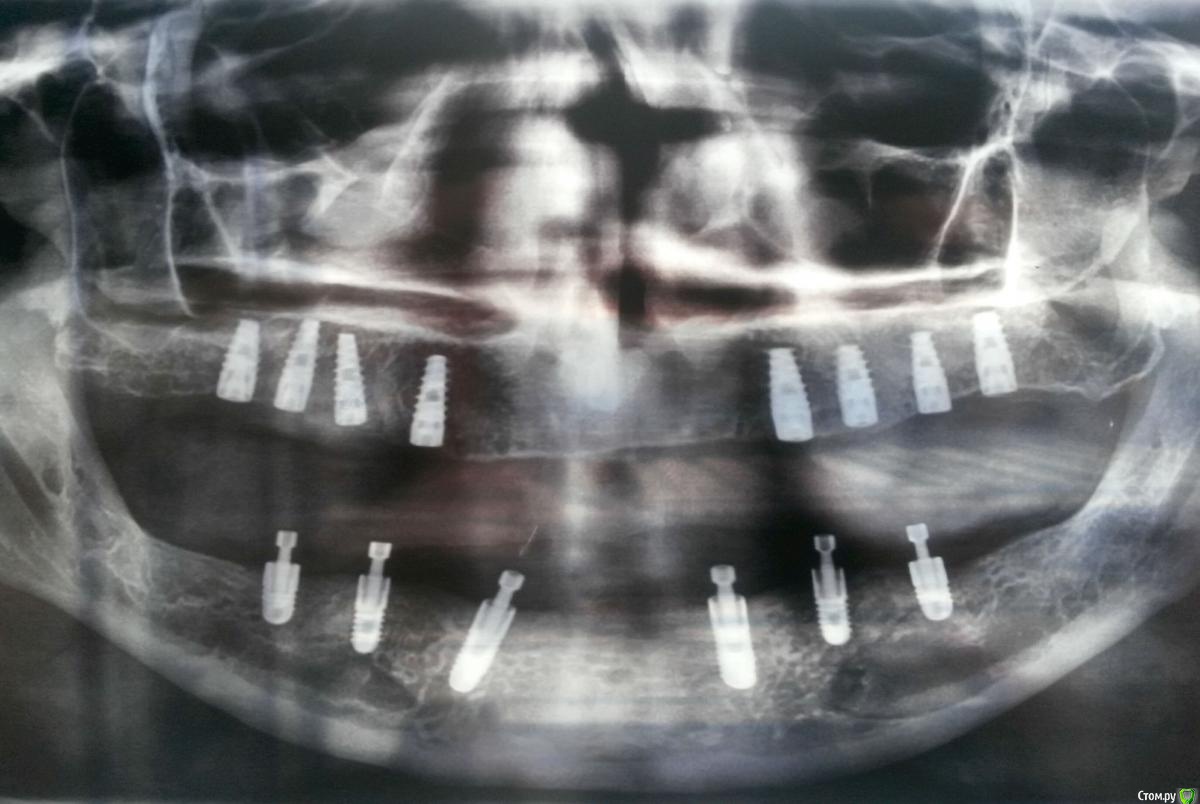

Cedric Опубликовано 17 января, 2018 Поделиться Опубликовано 17 января, 2018 (изменено) Добрый день! Мне предстоит полное протезирование верхней и нижней челюсти на имплантах, установленных по классической схеме.Протезирование планировалось проводить диоксидом циркония по технологии преттау, и тут, на первой примерке пластмассовых протезов, от врача поступило несколько неожиданное предложение - сделать протез для нижней челюсти из металлокомпозита. Обусловлено это было, во-первых, заботой о будущем моего сустава нижней челюсти, который может пострадать и расшататься из-за избыточной жесткости всей конструкции, и, во-вторых, тем, что сколы керамики всё равно будут, а металлокомпозит можно будет отреставрировать прямо во рту. Поскольку предложение было неожиданным, я сказал, что подумаю над этим вопросом, но, порывшись в интернете, ничего вразумительного не нашёл на этот счёт, зато наткнулся на ваш замечательный форум. Хотелось бы услышать комментарии специалистов по озвученным доводам. Неужели действительно полное протезирование диоксидом циркония не так уж и безобидно, и предложение моего врача не лишено смысла? Заранее благодарен за ответы. Прикладываю панорамный снимок, сделанный перед установкой формирователей десны в/ч. С уважением, Андрей. Изменено 17 января, 2018 пользователем Cedric Ссылка на комментарий